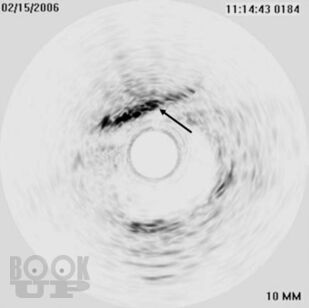

Часть II Кардиореабилитация на конкретных примерах описывает наиболее распространенные сердечные заболевания: ишемическая болезнь сердца с сахарным диабетом II типа или без него, инфаркт миокарда, случаи сердечной недостаточности в относительно стабильных условиях, при наличии или отсутствии устройств, контролирующих работу сердца и т.д.

- Представлены варианты диагностики и лечения разных заболеваний (коморбидные состояния, инфаркт миокарда, стенокардия, коронарное шунтирование, имплантация кардиостимулятора или водителя ритма, врожденный порок сердца, поражение периферических артерий) на примере репрезентативных клинических случаев.